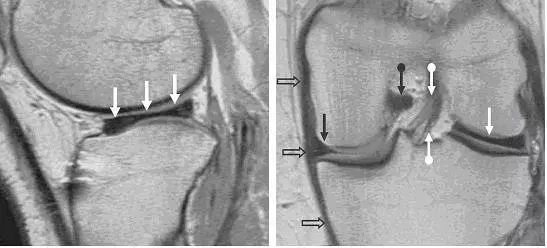

左图:矢状位片,可见外侧半月板(白色箭头)失去「领结样」形态,而呈现长条状,可与上图 2 左图对比。右图:冠状位片可更清楚对比,外侧半月板(白色直箭头)呈长条状而内侧半月板(黑色直箭头)呈正常的楔形。图中同时可看到其他软组织的相对关系,如前交叉韧带,可看到前交叉韧带前后束的明显分层(上下白色圆箭头),后交叉韧带(黑色圆箭头),内侧副韧带(空心箭头)。